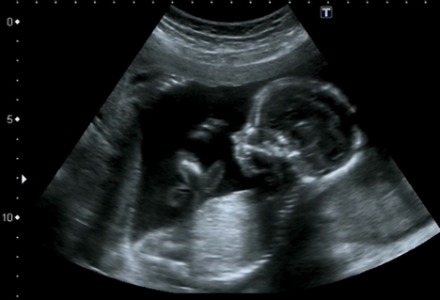

Η κυριότερη εφαρμογή τους είναι στα υπερηχογραφήματα τα οποία γίνονται με ειδικές συσκευές που χρησιμοποιούν υπερήχους για να απεικονίσουν το εσωτερικό του ανθρώπινου σώματος για τον εντοπισμό όγκων ή άλλων προβλημάτων.

Κάτι αντίστοιχο γίνεται στις έγκυες γυναίκες για την απεικόνιση του εμβρύου κατά τη διάρκεια της εγκυμοσύνης.